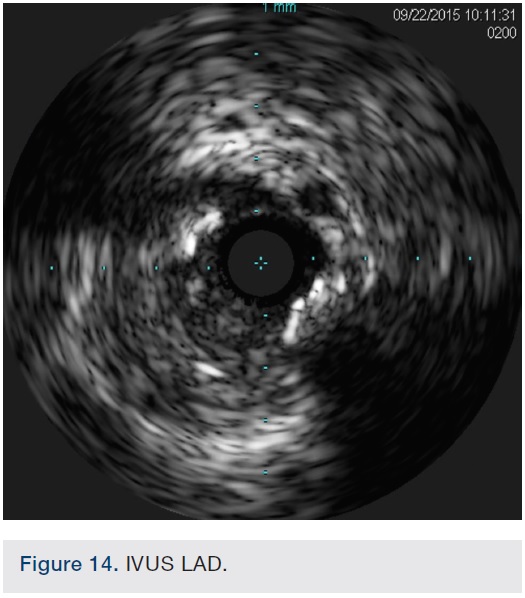

After undertaking initial medical optimization, the patient continued to have extensive symptoms with consumption of 5-6 nitroglycerin tablets (NTGs) on bad days and 2 NTGs on good days. Intravascular ultrasound (IVUS) of the LM was undertaken and this revealed a minimal lumen area (MLA) of 5.0 mm2, consistent with a significant LM stenosis (Figure 4). He was referred for coronary artery bypass grafting, but was felt to be a poor candidate due to his poor left ventricular (LV) systolic function. Therefore, we decided to undertake percutaneous coronary intervention (PCI) of his LAD and/or LM. The overall risk of complications of about 5-6% or so was discussed with patient, including the likely need for hemodynamic support.

Following successful completion of the peripheral phase, it was felt that a 4-week period was necessary for the iliac stent to heal somewhat (especially since we planned to place a 14 French Cook sheath through it). We then moved on to the coronary phase of this procedure. Bilateral groins and the right wrist were prepared and draped in the usual sterile fashion. Using micropuncture technique with fluoroscopic verification of needle entry into the left CFA at the upper quadrant of the femoral head, a 6 French sheath was placed in the left CFA. The existing left femoral arterial sheath was removed, and the arteriotomy was pre-closed with a single Perclose device (Abbott Vascular). The arteriotomy was then serially dilated with 10, 12 and 14 French dilators, and a 14 French, 30 cm Cook sheath was placed successfully in the left common femoral artery. Following therapeutic anticoagulation with intravenous heparin, a regular J-wire and a 6 French pigtail catheter were used to cross the aortic valve, and the catheter was used to exchange the J wire for the 0.018-inch Platinum Plus wire (Boston Scientific). The Impella CP (3.5) percutaneous left ventricular assist device (LVAD) (Abiomed) was inserted into the left ventricle over the Platinum Plus wire (Figure 8). The Impella was then activated and good flows were verified. Right radial artery access was obtained and a PB 3.0 7.5 French sheathless guide system (Asahi Intecc) was used to engage the left main coronary artery. The LAD was wired uneventfully using a Runthrough wire (Terumo) via a 1.25 x 6 mm over-the-wire (OTW) Sprinter balloon (Medtronic). This was then exchanged for a Viper wire (CSI). Orbital atherectomy of the proximal LAD lesion was performed with excellent results (80,000 rpm x 4 passes, 120,000 rpm x 2 passes) (Figure 9). The LAD wire was then exchanged for a Runthrough wire and the left circumflex (LCX) was wired with a BMW wire. Following plaque modification with orbital atherectomy, predilation of LAD was performed with 3.0 x 20 mm Chocolate Balloon (QT Vascular Ltd) (15 atmospheres x 60 seconds and 15 atmospheres x 30 seconds) (Figure 10) with an excellent result and no dissection (Figure 11). A 3.5 x 38 mm Promus stent (Boston Scientific) (14 atmospheres x 30 seconds) was placed from the left main into the proximal LAD lesion ensuring adequate coverage. The jailed LCX wire was recovered and re-placed in the LCX through the struts of the newly placed LM-LAD stent (Figure 12). Predilation of the LCX ostium was performed with a 2.5 x 8 mm Glider balloon (QT Vascular Ltd) (14 atmospheres x 25 seconds). The mid LAD was stented (ensuring overlap with proximal stent) with 3.0 x 16 mm Promus stent (16 atmospheres x 25 seconds). A final kissing balloon inflation of the LAD/LCX with an NC Sprinter 2.5 x15 mm balloon (Medtronic) into the LCX and a NC Sprinter 3.5 x12 mm balloon into the LAD was performed, with up to 16 atmospheres x 20 seconds on both (Figure 13). Final IVUS of the LM and LAD stent revealed excellent results and the LCX ostium looked excellent as well (Figures 14-16).